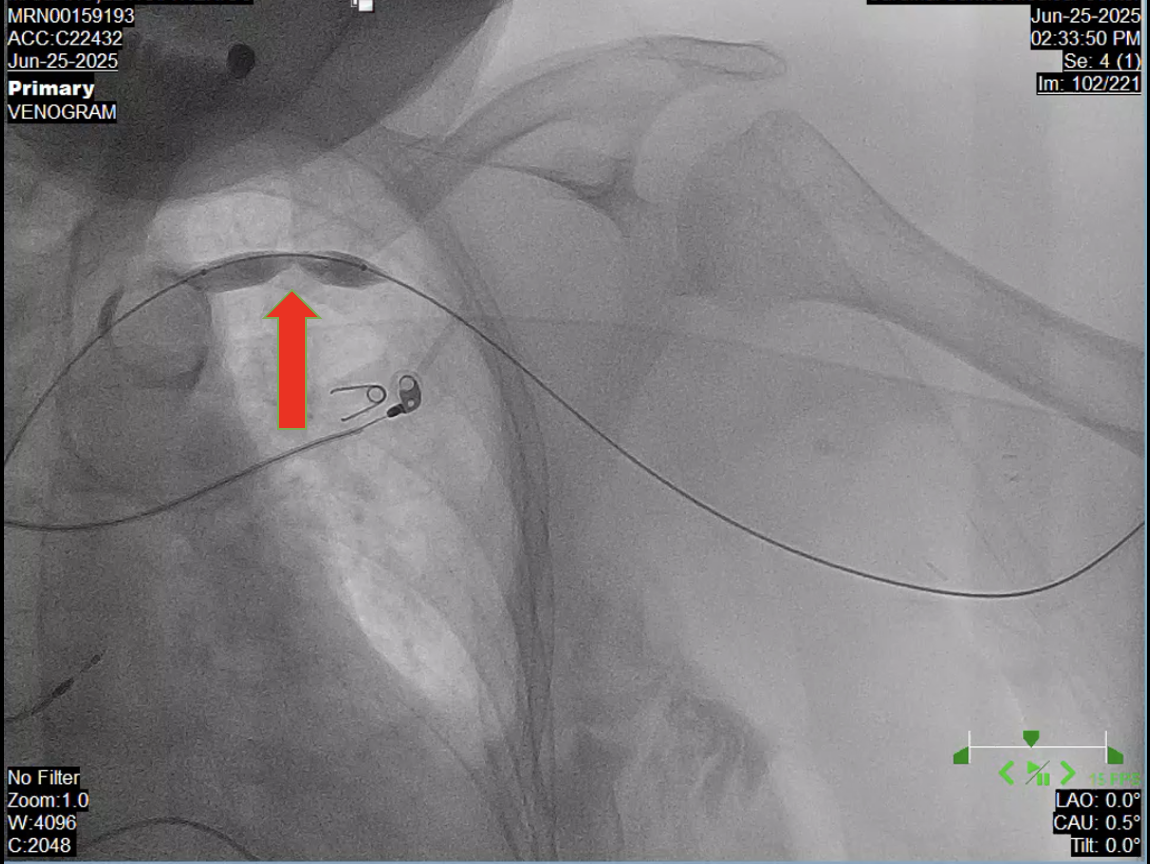

Left brachioaxillary graft was accessed using a Fr 4 hemostatic sheath. Venography done showing stenosis at the left subclavian vein at the level of the first rib. Mesurements taken with a degree of stenosis more than 95%. A balloon catheter was deployed using 10.0 x 40.0 mm Armada Abbott Catheter inflated at 10 atm for 30 seconds with gradual resolution of stenosis. Post venoplasty shots revealed normal contrast flow with disappearance of venous collaterals. No intraprocedural complications noted.